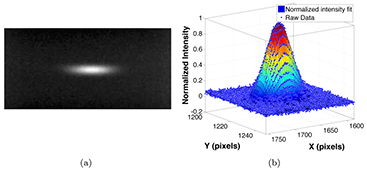

The source array used in the study was designed to have an anisotropic focal spot shape, as it was originally designed for non-medical applications. Figure 8(a) shows the pinhole image from a source. The magnification factor of the pinhole was calculated based on the magnification in size of the pinhole assembly. The intensity profile of the focal spot was measured, normalized, and fitted into a 2D Gaussian distribution, as shown in figure 8(b). The intensity was closely matched to a 2D Gaussian distribution, with a coefficient of determination (R2) of 0.9923, which agrees with the simulation results using electrical optics simulation model from our lab (Sultana et al 2010). The FWHM of the intensity profile was used as the focal spot size. Figure 9 shows a summary of the measured focal spot size of 5 sources in the source array and the relative difference to the average value. The FSSx refers to the focal spot size along the scanning direction (x-direction), while the FSSy is the focal spot size perpendicular to the scanning direction (y-direction). The measurement results show the focal spot size is consistent from source to source within 4% relative error, with an average FWHM of 2.5 × 0.5 mm, which agrees with the designed value for this particular source array.

Figure 8. Focal spot measurement using a pinhole. (a) shows the a typical pinhole image acquired at 80 kVp and 5 mA. The pinhole was 400 µm in diameter and 2 mm in thickness. (b) shows the normalized intensity and the 2D Gaussian fit of the focal spot distribution.

Download figure:

Standard image High-resolution imageFigure 9. Summary of the focal spot size measurement of 5 sources in the source array. The average focal spot size was measured as 2.5 × 0.5 mm. The results show a good source-to-source consistency, as the relative difference is less than 4%.